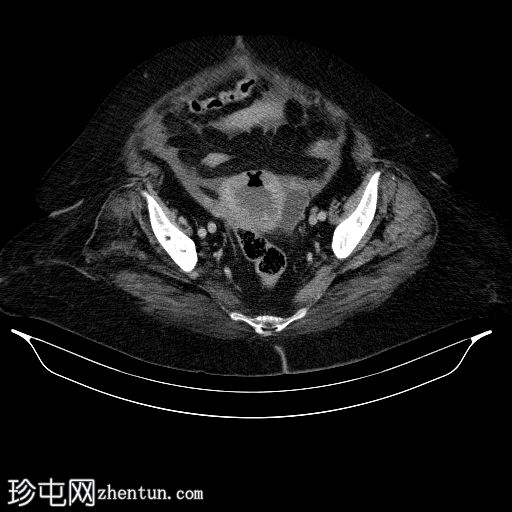

轴位增强扫描(门静脉期)

宫腔内可见气液平面,符合子宫蓄脓(宫腔内有脓液)。子宫前壁裂开,多个宫外气体灶延伸至腹膜外和腹膜内间隙,提示子宫穿孔。同时可见少量盆腔腹水和少量盆腔脂肪条索状改变。

其他发现:左侧附件囊肿、胆结石、双侧少量胸腔积液。